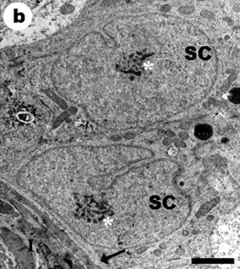

Ultraestructura

Con el microscopio electrónico, la célula de Sertoli (SC) muestra un núcleo celular con indentaciones y escotaduras en su membrana. La cromatina tiene gránulos dispersos y un nucléolo grande y central.

El citoplasma de la SC es abundante y con morfología cambiante, lo que hace difícil establecer las dimensiones mediante morfometría; en el ratón se ha estimado una longitud vertical (eje centrípeto) de 90 micrómetros (μm).

Contiene numerosos orgánulos por lo que su aspecto es más oscuro (electrodenso). Es abundante en mitocondrias, lo cual indica el alto grado de actividad metabólica que posee la célula.

El citoplasma de la SC presenta pliegues y prolongaciones que rodean a las espermatogonias y sostienen a los espermatocitos. Los procesos laterales pueden ser de tres tipos: los cónicos que se extienden desde la superficie lateral cerca de su base; los de forma de copa y los procesos aplanados en forma de lámina, que se extienden entre las células germinales redondas.

Son notorios los complejos de unión intercelular (uniones estrechas), en el sector basal entre los procesos cónicos de las SC, que determinan la barrera hemato-testicular con función de filtro.[10] [11]